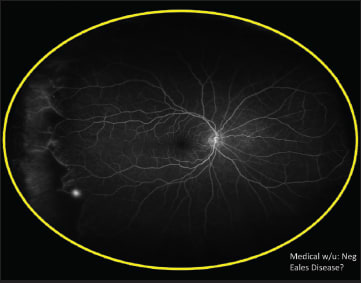

The second case Dr. Freund presented also used ultra widefield FA. This patient, a 55-year-old white woman, presented with what appeared to be posterior vitreous detachment–related symptoms, including the sudden onset of floaters related to a vitreous hemorrhage (Figure 1). The ultra widefield FA revealed instead that the problem arose from neovascularization related to peripheral nonperfusion; the fellow eye showed the same problem (Figures 2 and 3).

Figure 3. The fellow eye of the patient from Figures 1 and 2 also showed peripheral nonperfusion.